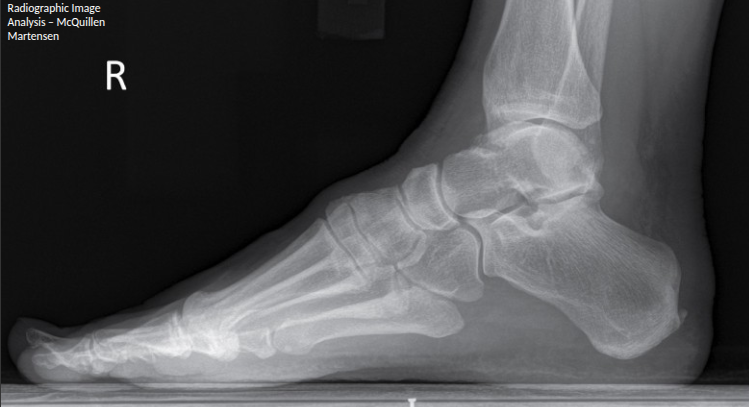

how should the fibula be on a lateral ankle

A

fibula in posterior half of tibia